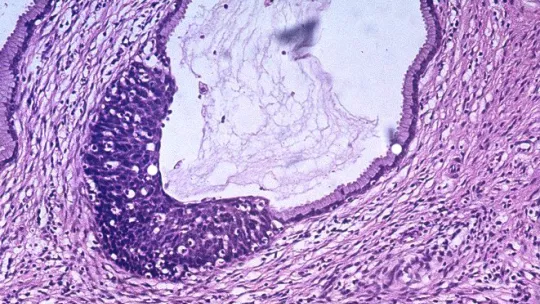

El programa de ciencia, investigación e innovación de Catalunya Informació "La poma de Newton", conducido por Purificación Barceló, se hace eco del estudio liderado por el investigador ICREA Salvador Aznar Benitah, líder del Laboratorio de Células Madre y Cáncer del IRB Barcelona, que identifica las células responsables de iniciar y promover metástasis en varios tipos de tumores humanos.

"Cuando los tumores de pacientes con una predisposición para generar metástasis son estimulados con una dieta rica en grasa o con niveles más altos de palmítico, se vuelven más agresivos. Dependiendo del paciente, un tumor es 10 o 15 veces más metastásico si se le alimenta con niveles más elevados de estas grasas ", explica Salvador Aznar Benitah.